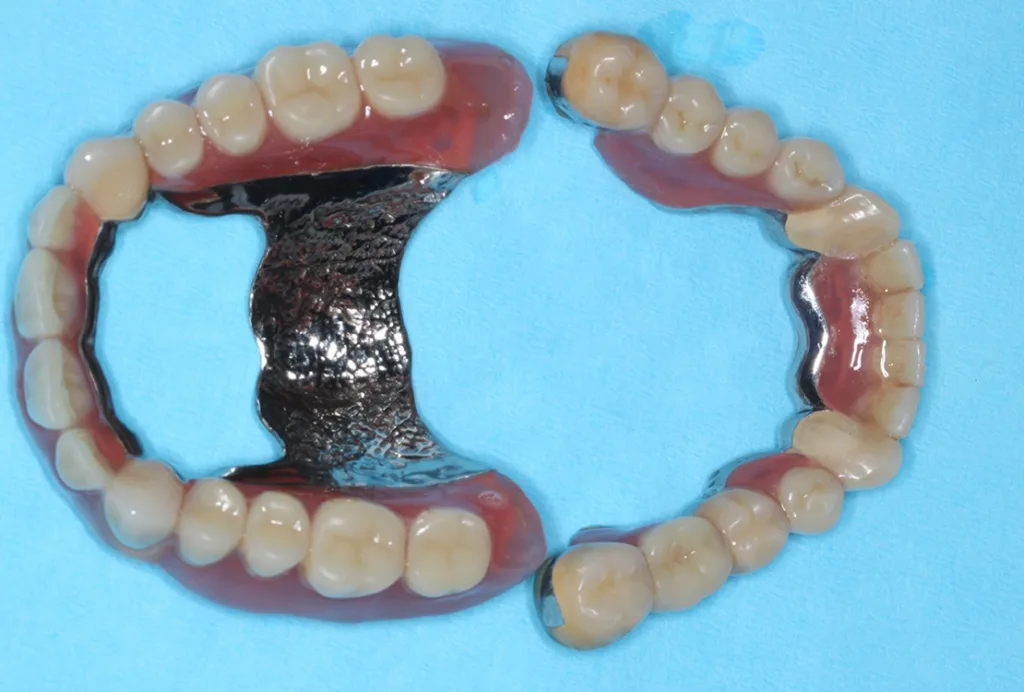

Abb. 3 a–e: Klinische Dokumentation eines 63-jahrigen männlichen Patienten (geb. 05.09.1961). Die Fotodokumentation erfolgte erst am Tag der AIT und nicht im Rahmen der klinischen und radiologischen und 47 wurden vor der AIT entfernt. An den Zahnen 13 und 23 war neben der peniblen subgingivalen Instrumentierung die Applikation von Straumann® Emdogain® (Straumann Group, Basel, Schweiz) vorgesehen.Walter

Abb. 3 a–e: Klinische Dokumentation eines 63-jahrigen männlichen Patienten (geb. 05.09.1961). Die Fotodokumentation erfolgte erst am Tag der AIT und nicht im Rahmen der klinischen und radiologischen und 47 wurden vor der AIT entfernt. An den Zahnen 13 und 23 war neben der peniblen subgingivalen Instrumentierung die Applikation von Straumann® Emdogain® (Straumann Group, Basel, Schweiz) vorgesehen.

Es handelt sich hierbei um einen 63-jährigen männlichen Patienten (geb. 05.09.1961). Allgemeinmedizinisch war eine rheumatoide Erkrankung und die Einnahme von Methotrexat (Folsäureantagonist, Zytostatikum und Immunsuppressivum) dokumentiert. Etwaige orale Nebenwirkungen dieser Medikation lagen nicht vor. Herr B. war Nichtraucher. Der Patient wünschte maximalen Zahnerhalt und wurde daher zur parodontalen Therapie der bereits weit fortgeschrittenen Parodontitis an eine spezialisierte Praxis überwiesen. Zu diesem Zeitpunkt waren im Oberkiefer noch 2 und im Unterkiefer noch 5 Zähne vorhanden.

Der Patient wurde über die Krankheitsentstehung, die Prognosen der Einzelzähne und die therapeutischen Optionen aufgeklärt. Es wurde eine systematische parodontale Therapie unter Berücksichtigung der aktuellen EFP/ DGParo-Leitlinien geplant [48]. Der radiologisch sichtbare Knochenverlust an den Zähnen 37 und 47 ging bereits weit über den Apex hinaus. Eine parodontale Therapie erschien daher nicht mehr erfolgversprechend. Die Zähne wurden vor der antiinfektiösen Therapie (AIT) extrahiert und die Alveolen mit adaptierenden Nähten stabilisiert. Im Rahmen der Unterweisungen für eine optimierte häusliche Mundhygiene wurde dem Patienten die Benutzung einer Monobüschelbürste demonstriert und empfohlen. Bei regelmäßiger Anwendung an den vereinzelten, mit Primärteleskopen versorgten Zähnen lassen sich auch diese Zähne in ihrer gesamten Zirkumferenz sehr gut reinigen. Bei den verbliebenen 5 Zähnen war geplant, die zur Verfügung stehenden nichtchirurgischen Möglichkeiten auszuschöpfen. Eine adjuvante Gabe von systemischen Antibiotika war allerdings nicht vorgesehen. Das bedeutete aber, dass im Oberkiefer an den besonders schwer vorgeschädigten Zähnen 13 und 23 neben der subgingivalen Instrumentierung mit Ultraschall und Pulverwasserstrahl (EMS, Nyon, Schweiz) zusätzlich SMP (Straumann® Emdogain®, Basel, Schweiz) appliziert werden sollten [50]. Da beide Zähne einen erhöhten Lockerungsgrad aufwiesen, bestünde die Notwendigkeit einer präoperativen Schienung spätestens vor einer möglichen chirurgischen Stufe-3-Therapie.

Der Punkt, dass beide Zähne demzufolge wohl eher nicht unter optimalen Bedingungen parodontalchirurgisch operiert werden können, hat daher auch zu der Entscheidung einer SMP/EMD-Anwendung in der AIT beigetragen. Die AIT wurde an einem Termin durchgeführt. Nach der Applikation einer Lokalanästhesie wurden alle Zähne zunächst mit Ultraschall und nach Detektion glatter und harter Wurzeloberflächen mit einem erythritolhaltigen Pulverwasserstrahlgemisch mit dem Standard-Handstück behandelt (EMS, Nyon, Schweiz). An den Zähnen 13 und 23 wurden in derselben Sitzung noch zusätzlich SMP – entsprechend einem von Prof. A. Kašaj publiziertem Protokoll (Abb. 5) – appliziert. Zuvor wurde eine Blutstillung unter Verwendung von H2O2 und dem Einbringen von sterilisiertem Superfloss vorgenommen und ein EDTA-Gel zur Konditionierung der Wurzeloberfläche appliziert. Das Aufbringen von Histoacryl® (B. Braun, Tuttlingen, Deutschland) Gewebekleber zum Verschluss der instrumentierten parodontalen „Taschen“ rundete diesen Behandlungszyklus ab. Das detaillierte Vorgehen bei diesem Patienten ist in den Abbildungen 4a–j dargestellt. Da die Zähne nicht geschient werden konnten, wurde der Patient instruiert, auf ein Herausnehmen und Wiedereinsetzen der Prothese sofern möglich in den nächsten Tagen zu verzichten. Nach der AIT wurde die supragingivale Plaquekontrolle an 3 Terminen kontrolliert und die Wundheilung durch professionelle Zahnreinigungen unterstützt.